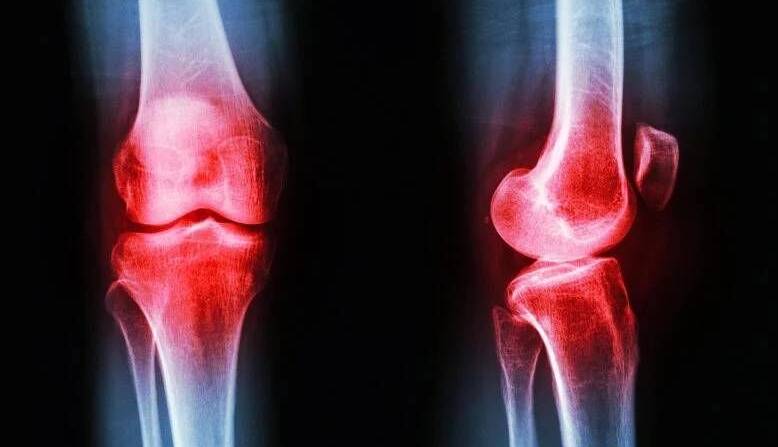

تحرک؛ قوی‌ترین درمان آرتروز

ایرنا/اگر فکر می‌کنید درمان آرتروز فقط به قرص‌های مسکن و جراحی ختم می‌شود، سخت در اشتباهید. تحقیقات جدید نشان می‌دهد مؤثرترین سلاح برای مقابله با این بیماری، تحرک است که کاملاً رایگان و در دسترس همه است.

آرتروز شایع‌ترین بیماری مفاصل در جهان است که بیش از ۵۹۵ میلیون نفر را تحت تأثیر قرار داده است. یک تحلیل جهانی مهم در مجله معتبر لَنسِت/ Lancet هشدار می‌دهد تعداد مبتلایان تا سال ۲۰۵۰ میلادی می‌تواند به نزدیک یک میلیارد نفر برسد. طول عمر بیشتر، زندگی کم‌تحرک و افزایش چاقی، همگی در این روند صعودی نقش دارند.